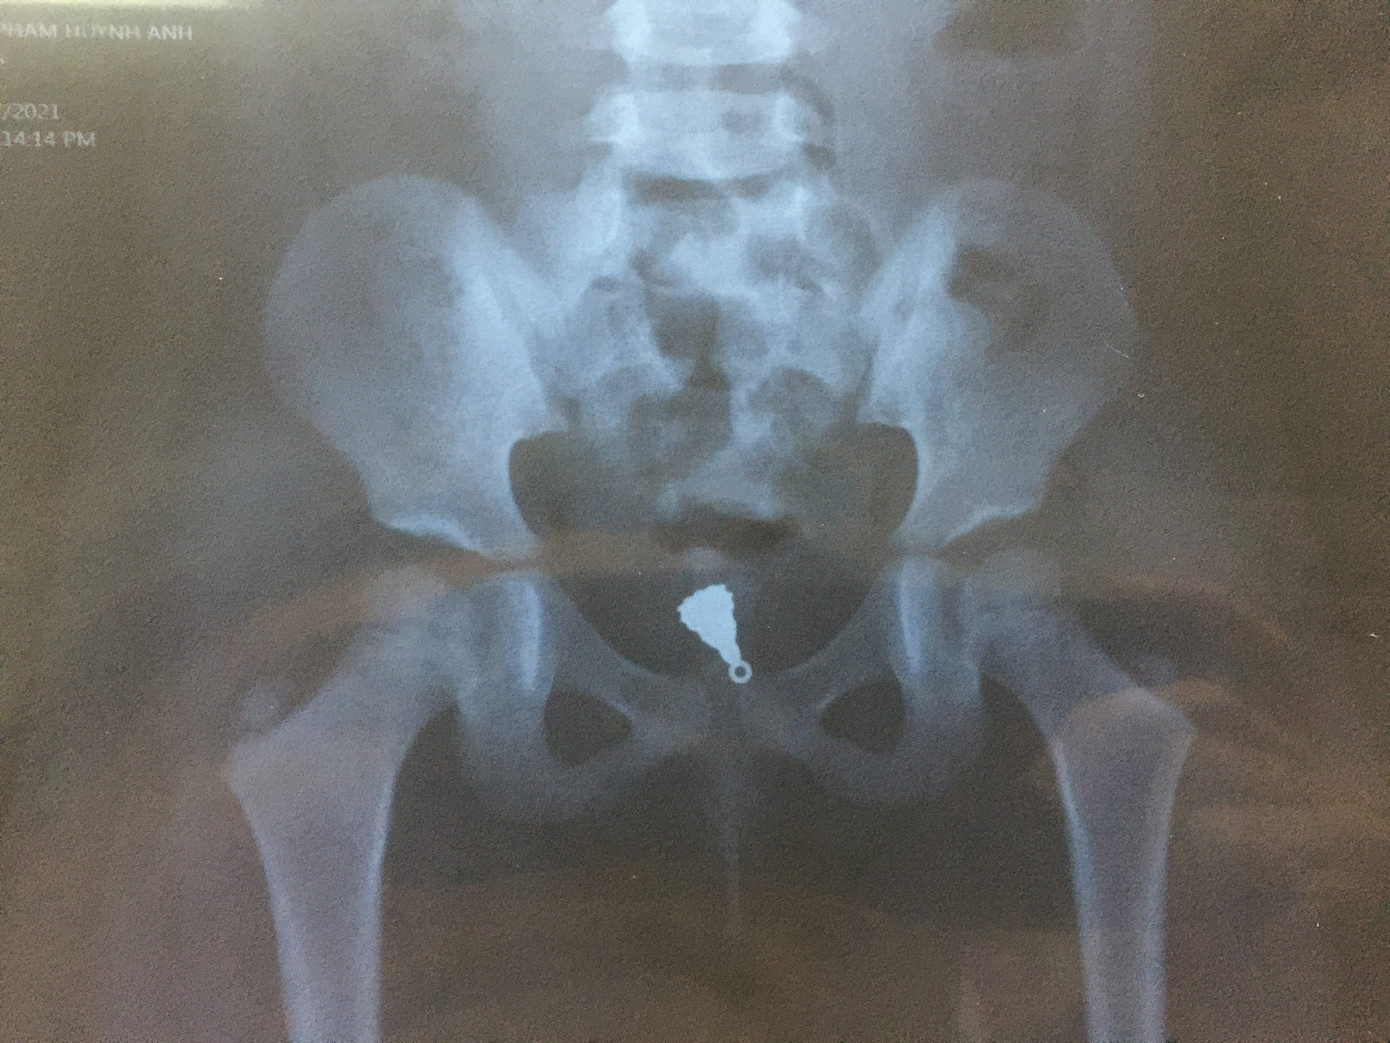

Thời điểm nhập viện, bệnh nhi không còn chảy máu vùng âm đạo. Tuy nhiên, thám sát tiền đình thấy trầy sướt nhẹ. Tiến hành chụp phim Xquang vùng bụng chậu cản quang thì phát hiện ở vùng tiểu khung có dị vật dạng mặt dây chuyền.

Mặt dây chuyền nằm trong âm đạo bé gái.